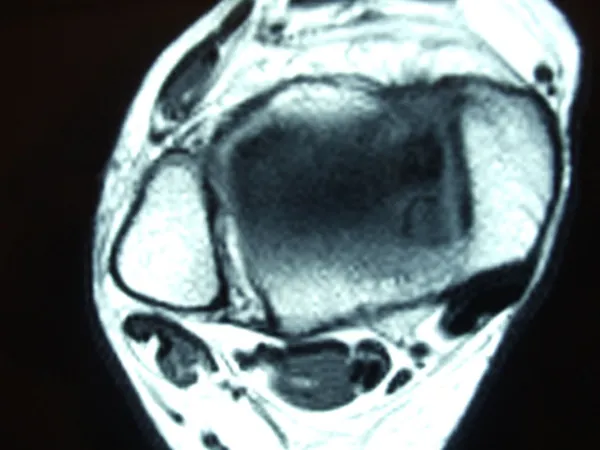

Series of Pics of Microfracture of large OCD of the Talar Dome

Pic of OCD after preparation and debridement .

Measuring the size and depth of the OCD.